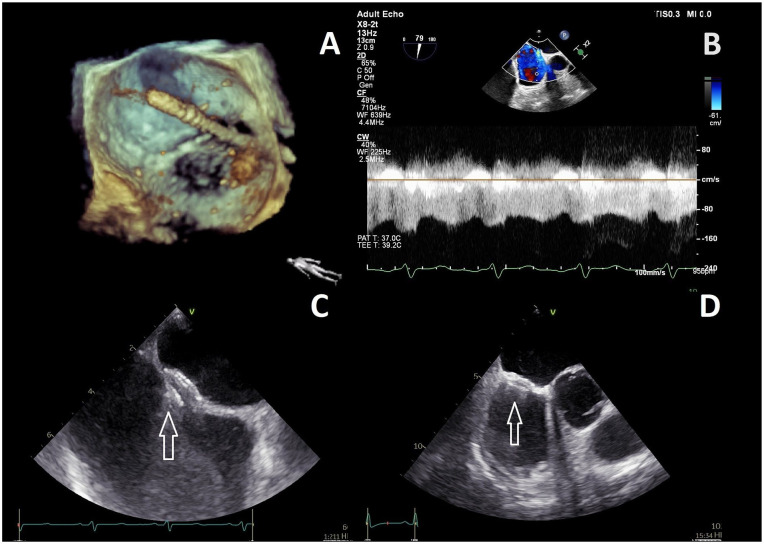

Introduction: Iatrogenic atrial septal defect (iASD) resulting from MitraClip procedures may cause volume overload and deterioration of right ventricular (RV) function. The concurrent MitraClip procedure, along with an intervention to close iASD appears to yield a potentially favorable impact on the functioning of the right ventricle.

Aim of the study: The study aims to evaluate the effect of iASD closure with an occluder immediately after the MitraClip procedure on RV function, pulmonary resistance, and right ventricle-pulmonary artery coupling (RV-PAc).

Methods: The study group (ASDc) consisted of consecutive patients who underwent concomitant iASD closure with the Amplatzer occluder (n = 10). The control group (n = 9) comprised patients with iASD left untreated (CT group). RV assessment before MitraClip and during follow-up visits was based on transthoracic echocardiography (TTE).